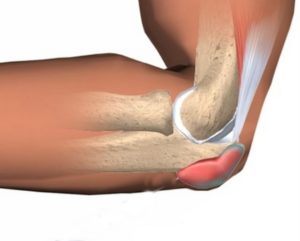

Синовиальнаясумка – это структура (грубо говоря, мешок из толстой скользкой ткани),позволяющая частям тела двигаться плавно относительно друг друга. Синовиальныесумки располагаются там, где кожа, мышцы или сухожилия должны скользить надкостью. Они смазываются небольшим количеством жидкости, которая помогает снизитьтрение между скользящими поверхностями.

Синовиальная сумка локтевого отростка расположена между локтевым отростком локтевой кости и кожей. Она позволяет локтевому суставу свободно сгибаться и разгибаться под кожей. Когда синовиальная сумка раздражена, то она наполняется жидкостью, что ведет к отеку кончика локтевого отростка и препятствует движениям локтя.

Бурса локтевого отростка — это анатомическое образование, мешок, находящийся выше локтевого отростка под кожей. Она имеет синовиальную оболочку, но не сообщается с окружающими тканями. Она снижает трение между кожей, сухожилием трехглавой мышцы плеча, связками и костями при движении, и позволяет им плавно скользить относительно друг друга [1,2,3].